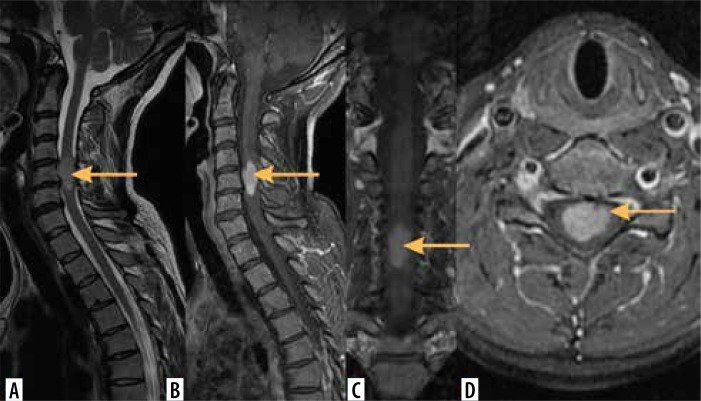

髓内肿瘤(IMTs)是椎管最不常见的肿瘤。其中大多数是室管膜瘤和星形细胞瘤,第三常见的是血管母细胞瘤,而脊髓的其他肿瘤相对罕见。本文综述了脊髓肿瘤影像学的最新进展。磁共振成像(MRI)是诊断imt的首选成像方法,其他方式起辅助作用。作者讨论了IMTs的MRI方案,包括先进的技术,并介绍了特定肿瘤的成像特征。本文还介绍了IMTs与其他脊髓疾病的区别。

Intramedullary tumours (IMTs) are the least common neoplasms of the spinal canal. The majority of them are ependymomas and astrocytomas, the third commonest is haemangioblastoma, while other tumours of the spinal cord are relatively rare. This review presents on update on the imaging of spinal cord tumours. Magnetic resonance imaging (MRI) is the imaging method of choice in diagnosing IMTs, with other modalities playing a supplementary role. The authors discuss the MRI protocol in IMTs including advanced techniques and present the imaging features of particular tumours. The differentiation of IMTs from other spinal cord diseases is also presented.